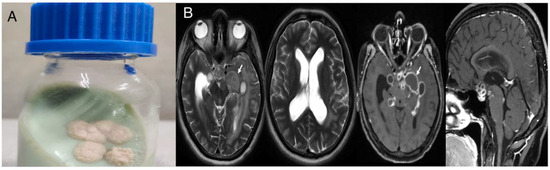

Case 1

Case 2